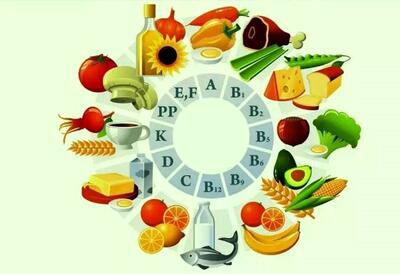

جگر مرغ یکی از اعضای داخلی بدن مرغ است که سرشار از مواد مغذی مانند آهن، ویتامین A، ویتامین B12، فولات و پروتئین است. اما یکی از نگرانیهای رایج در مورد مصرف جگر مرغ، احتمال تجمع هورمونها و سموم در آن است.

مواد غذایی حاوی B12 کدامند؟

بهترین مواد غذایی برای تامین ویتامین B12 کدامند؟

ویتامین B12، یک ویتامین ضروری برای بدن، به ویژه برای سلامت مغز و سیستم عصبی، بسیار مهم است. بسیاری از افراد برای تامین این ویتامین

گوشت قرمز منبعی غنی از آهن، پروتئین و ویتامین B12 است که با مصرف متعادل، میتواند به تقویت سیستم ایمنی و سلامت بدن در فصل زمستان کمک کند.

ویتامین ب12 به طور طبیعی در محصولات حیوانی یافت می شود و برای درمان آکنه صورت و جوش از آن استفاده بسیاری می شود.